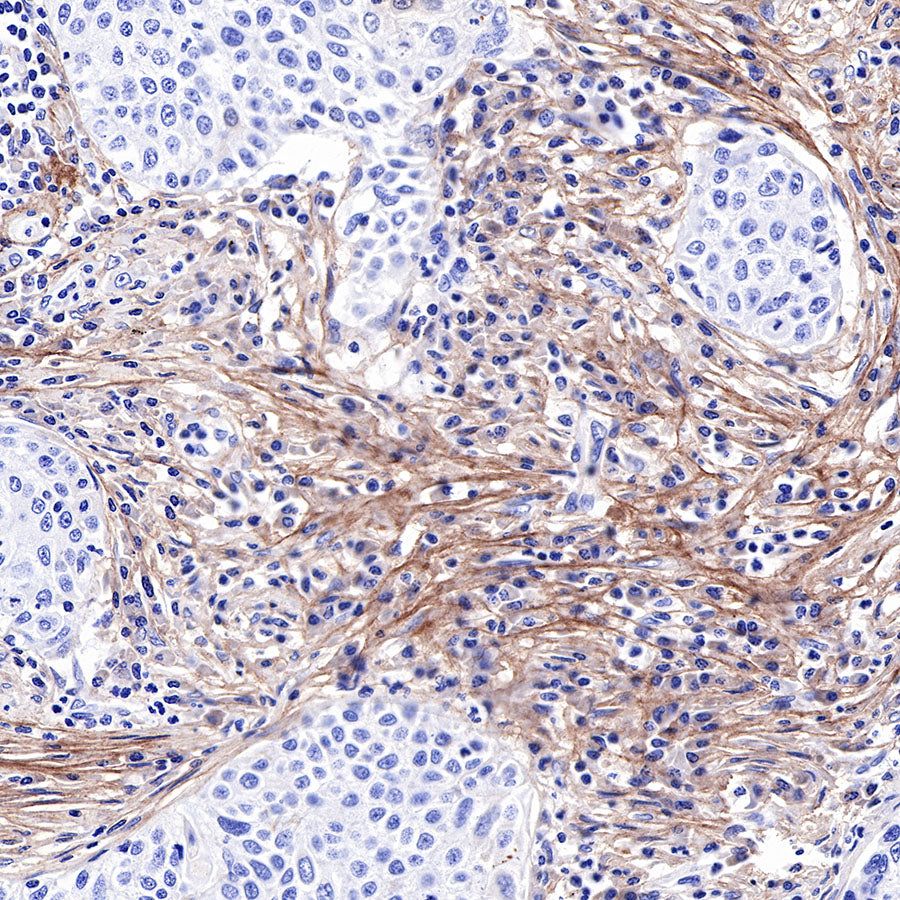

IHC shows positive staining in paraffin-embedded human pancreatic cancer. Anti-COL3A1(PIIINP) antibody was used at 1/500 dilution, followed by a HRP Polymer for Mouse & Rabbit IgG (ready to use). Counterstained with hematoxylin. Heat mediated antigen retrieval with Tris/EDTA buffer pH9.0 was performed before commencing with IHC staining protocol.